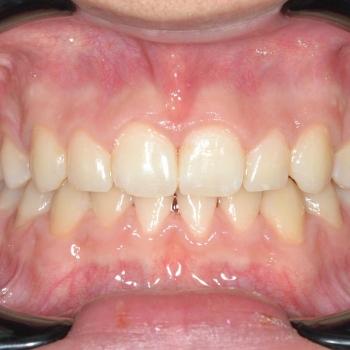

Nándi kitartásának és az előre megtervezett lépéseknek hála tökéletes funkciót és esztétikai végeredmény értünk el.

A kezelés teljes időtartama: 2 év 6 hónap